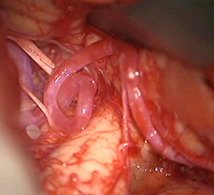

左後下小脳動脈(矢印)は術後に本来の位置から移動している。

舌咽神経への血管圧迫が解除されたため、術後に患者様は舌咽神経痛が消失した。